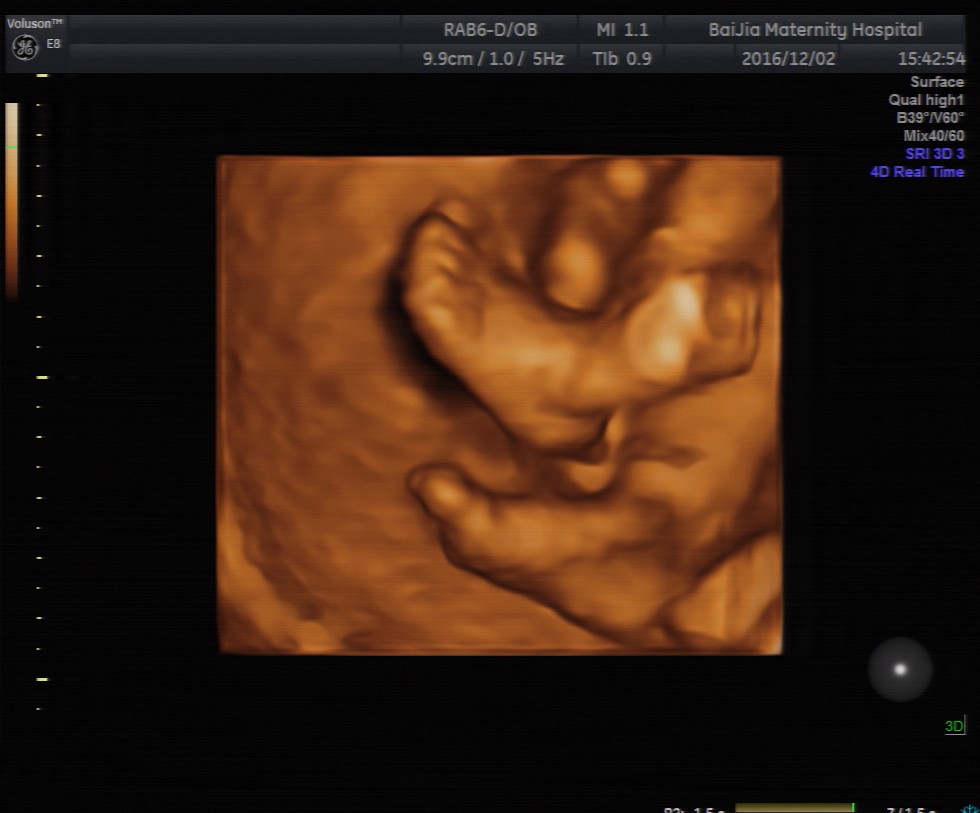

理论上来讲,孕20—24周是做四维彩超的最佳时间,这个时期是胎儿的快速发育时期,胎儿的基本结构已经形成。同时,适中的胎儿大小及羊水量,给胎儿提供了较大的活动空间,有利于全方位观察胎儿的活动状态。

除了观察胎儿的活动情况,孕中期对胎儿做四维彩超的主要目的是筛查胎儿结构畸形。